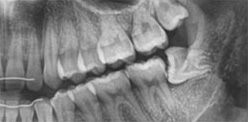

02 / X-Ray

검진 후 X-Ray 촬영 후 사랑니의 상태 확인 평가 후 계획을 수립합니다.